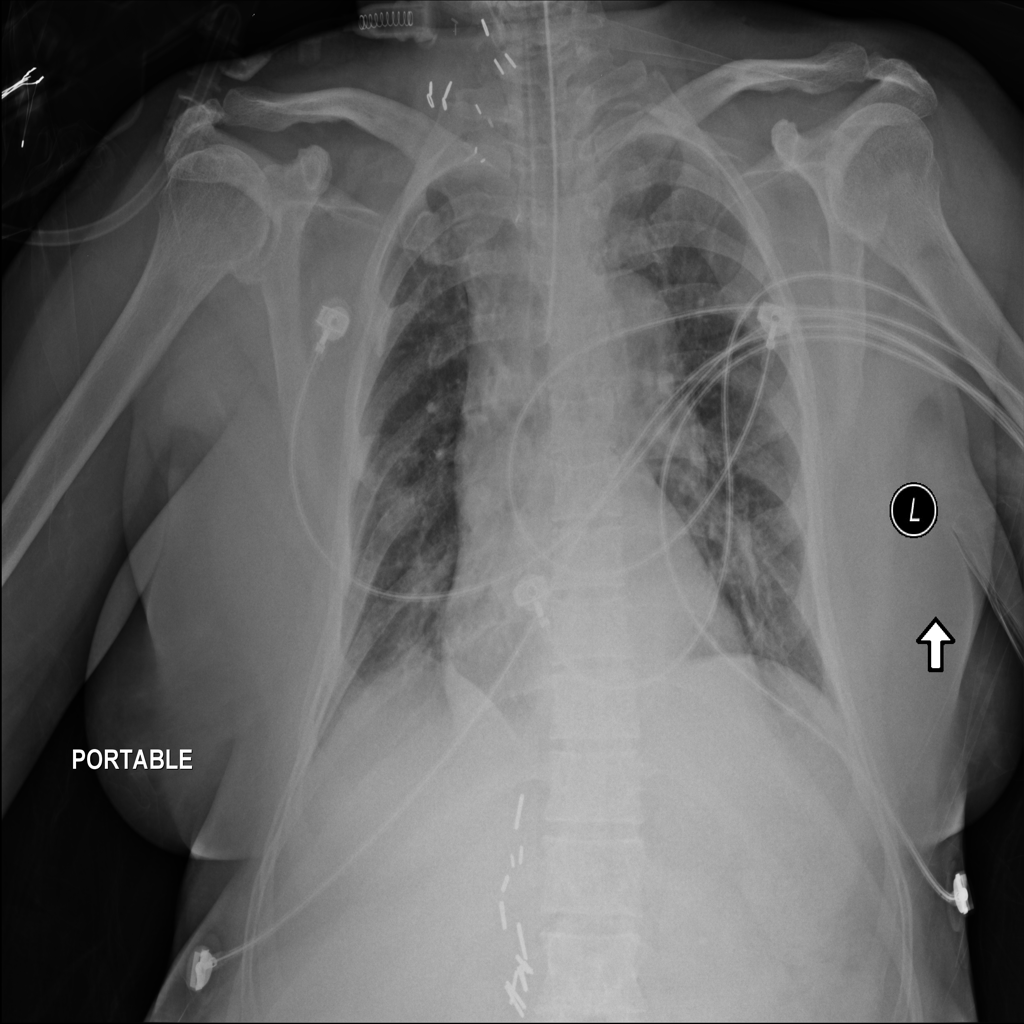

Mass

A mass is a larger focal opacity or lesion seen on the image. It is a descriptive finding that can have several causes and usually needs more imaging or clinical context to characterize.

PAT-2519 · IMG-021Mass

PAT-2519 · IMG-021

AP